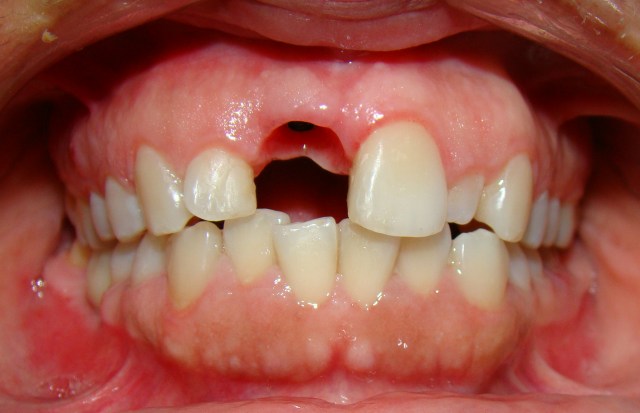

» Caso 2 - Implante e Estética

Paciente sofreu fratura do elemento 11 (incisivo central) e foi reabilitada com implante e pr&oa...